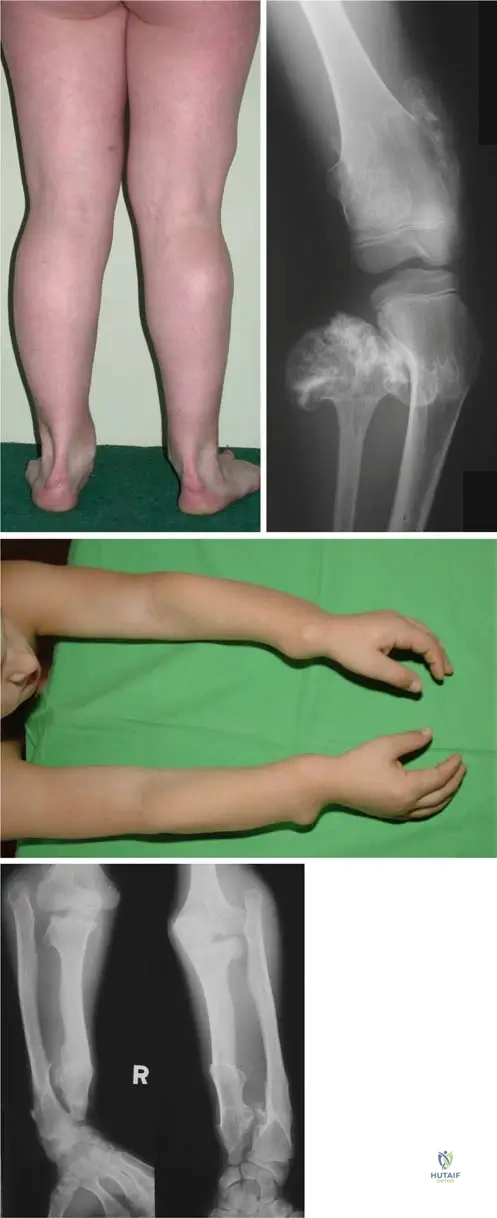

A 7-year-old girl with hereditary multiple exostoses is noted to have progressive bowing of her forearms and ulnar deviation of her wrists. Radiographs confirm multiple osteochondromas in the distal radius and ulna. Which of the following is a common associated deformity seen in HME affecting the upper extremities?

Correct Answer: B

Rationale: Severe deformation of forearms with bilateral elbow dislocation is a recognized complication of hereditary multiple exostoses, as shown in Fig. 1.53d. The bowing of the radius with ulnar deviation of the wrist and subluxation of the radiocarpal joint are also common. While other conditions listed can occur in the upper extremity, radial head dislocation (often leading to elbow dislocation) is a direct and common consequence of the growth disturbances caused by osteochondromas in the forearm in HME.

Question 52

A 5-year-old boy with hereditary multiple exostoses is observed to have a progressive valgus deformity of his knees. Physical examination confirms bilateral genu valgum. Radiographs show multiple osteochondromas around the distal femurs and proximal tibias. Which of the following deformities is commonly observed around the knee joint in patients with HME?

View Answer & Explanation

Correct Answer: C

Rationale: Valgus deformities of the knee and ankle are explicitly mentioned as common deformities in patients with hereditary multiple exostoses. Osteochondromas around the knee joint can lead to malalignment of the axis, frequently resulting in genu valgum. Genu varum is less common, and the other options are not specifically highlighted as common knee deformities in HME.